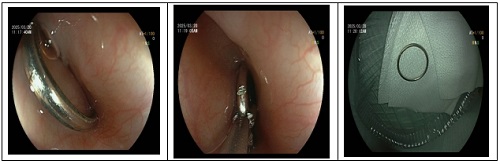

内镜下开展的手术

2.内镜下异物取出术